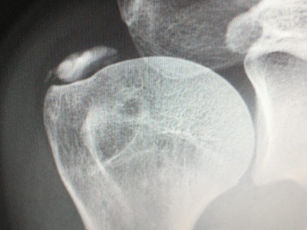

Dor no quadril e a medicina intervencionista

Dor no quadril e a medicina intervencionista. Em alguns textos aqui no site irei abordar, de forma ilustrativa e superficial, algumas...